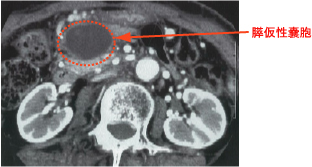

▼膵仮性嚢胞

膵炎や外傷により生じます。

仮性嚢胞なので上皮はなく結合組織で覆われています。

内容物は膵液(膵酵素)、滲出液、粘液、血液などの混合物です。

超音波やCTで嚢胞を確認できます。